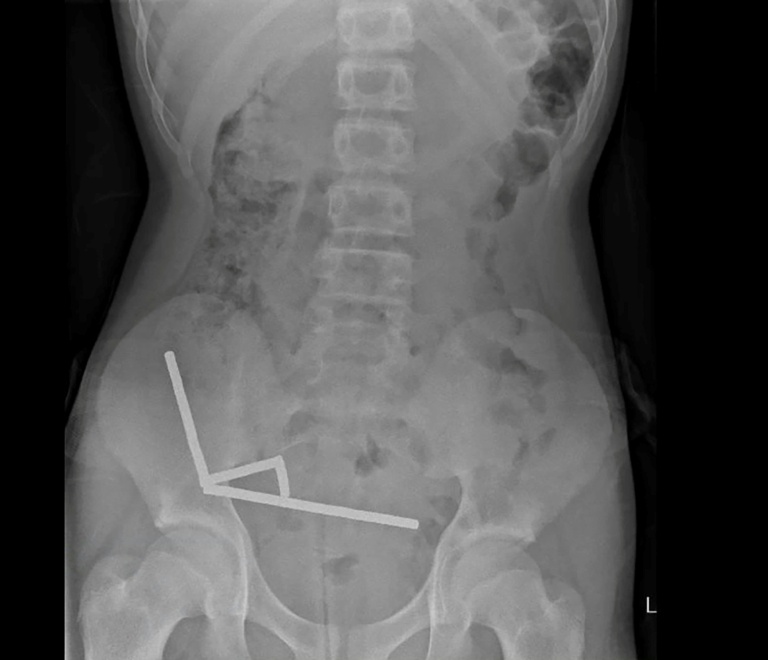

Doctors identified the magnets clumped together in four straight lines within the child’s intestines, which they noted were “adhered together due to magnetic forces.” The pressure exerted by the magnets caused necrosis, or tissue death, in several areas of the boy’s small bowel and caecum, a part of the large intestine.

Surgeons performed an operation to remove the dead tissue and extract the magnets. The unnamed boy spent eight days in the hospital but was ultimately able to return home. The authors of the medical paper, Binura Lekamalage, Lucinda Duncan-Were, and Nicola Davis, emphasized that this case illustrates the dangers associated with magnet ingestion and the risks presented by online marketplaces for children.